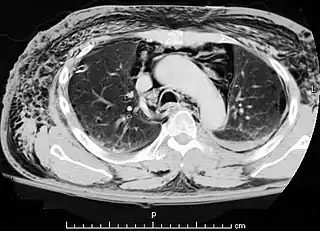

![]() Una TAC que muestra aire en el mediastino | ||

El neumomediastino se define como la presencia de aire en el mediastino observado mediante una radiografía o prueba de imagen mediante TAC[1]. Normalmente ocurre cuando el aire sale de la vía aérea, el pulmón o el esófago y entra en esta cavidad.